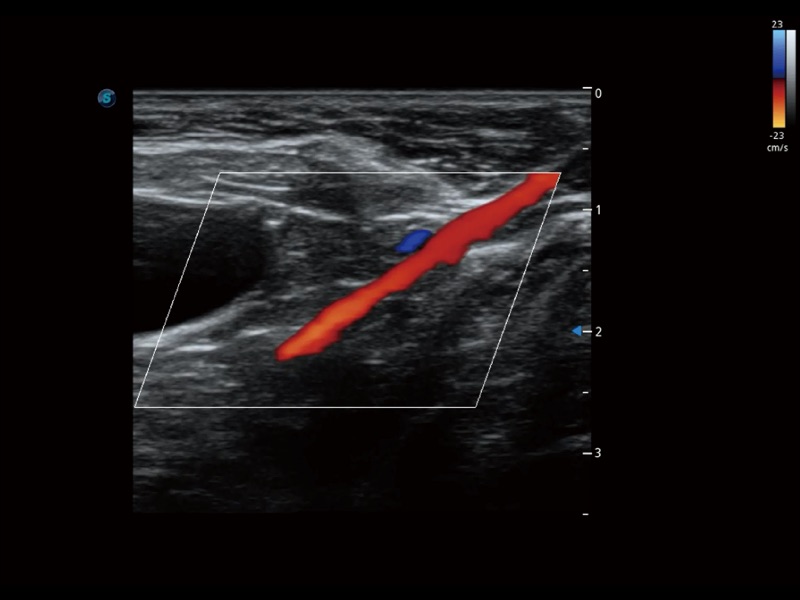

通過創(chuàng)新的 Matrix E自適應(yīng)濾波器和超長時(shí)間域算法,極大提升超低速微細(xì)血流的檢出能力,同時(shí)更精準(zhǔn)地濾除軟組織和噪聲信號,為獸用醫(yī)生提供以往無法通過常規(guī)血流獲得的疾病診斷信息。

通過色彩血流和實(shí)時(shí)寬景相結(jié)合,可觀察到完整的靜脈或動脈的血流,方便醫(yī)生檢查。實(shí)時(shí)掃查過程中,如有任何操作失誤也可以很容易地進(jìn)行回掃擦除,而不會中斷掃查。